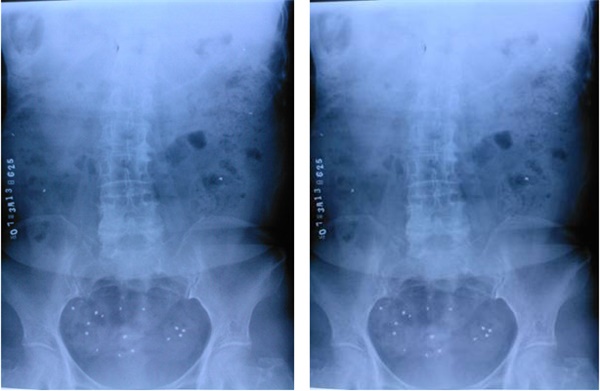

2、结肠传输试验

结肠传输试验是检查人体结肠传输功能的一种方法。通过口服不透X光标记物,使其混合于肠内容物中,在比较接近生理条件的前提下,分别于口服标记物后24小时、48小时及72小时摄片,观察结肠的运动情况.

结肠传输试验阴性

结肠传输试验阳性